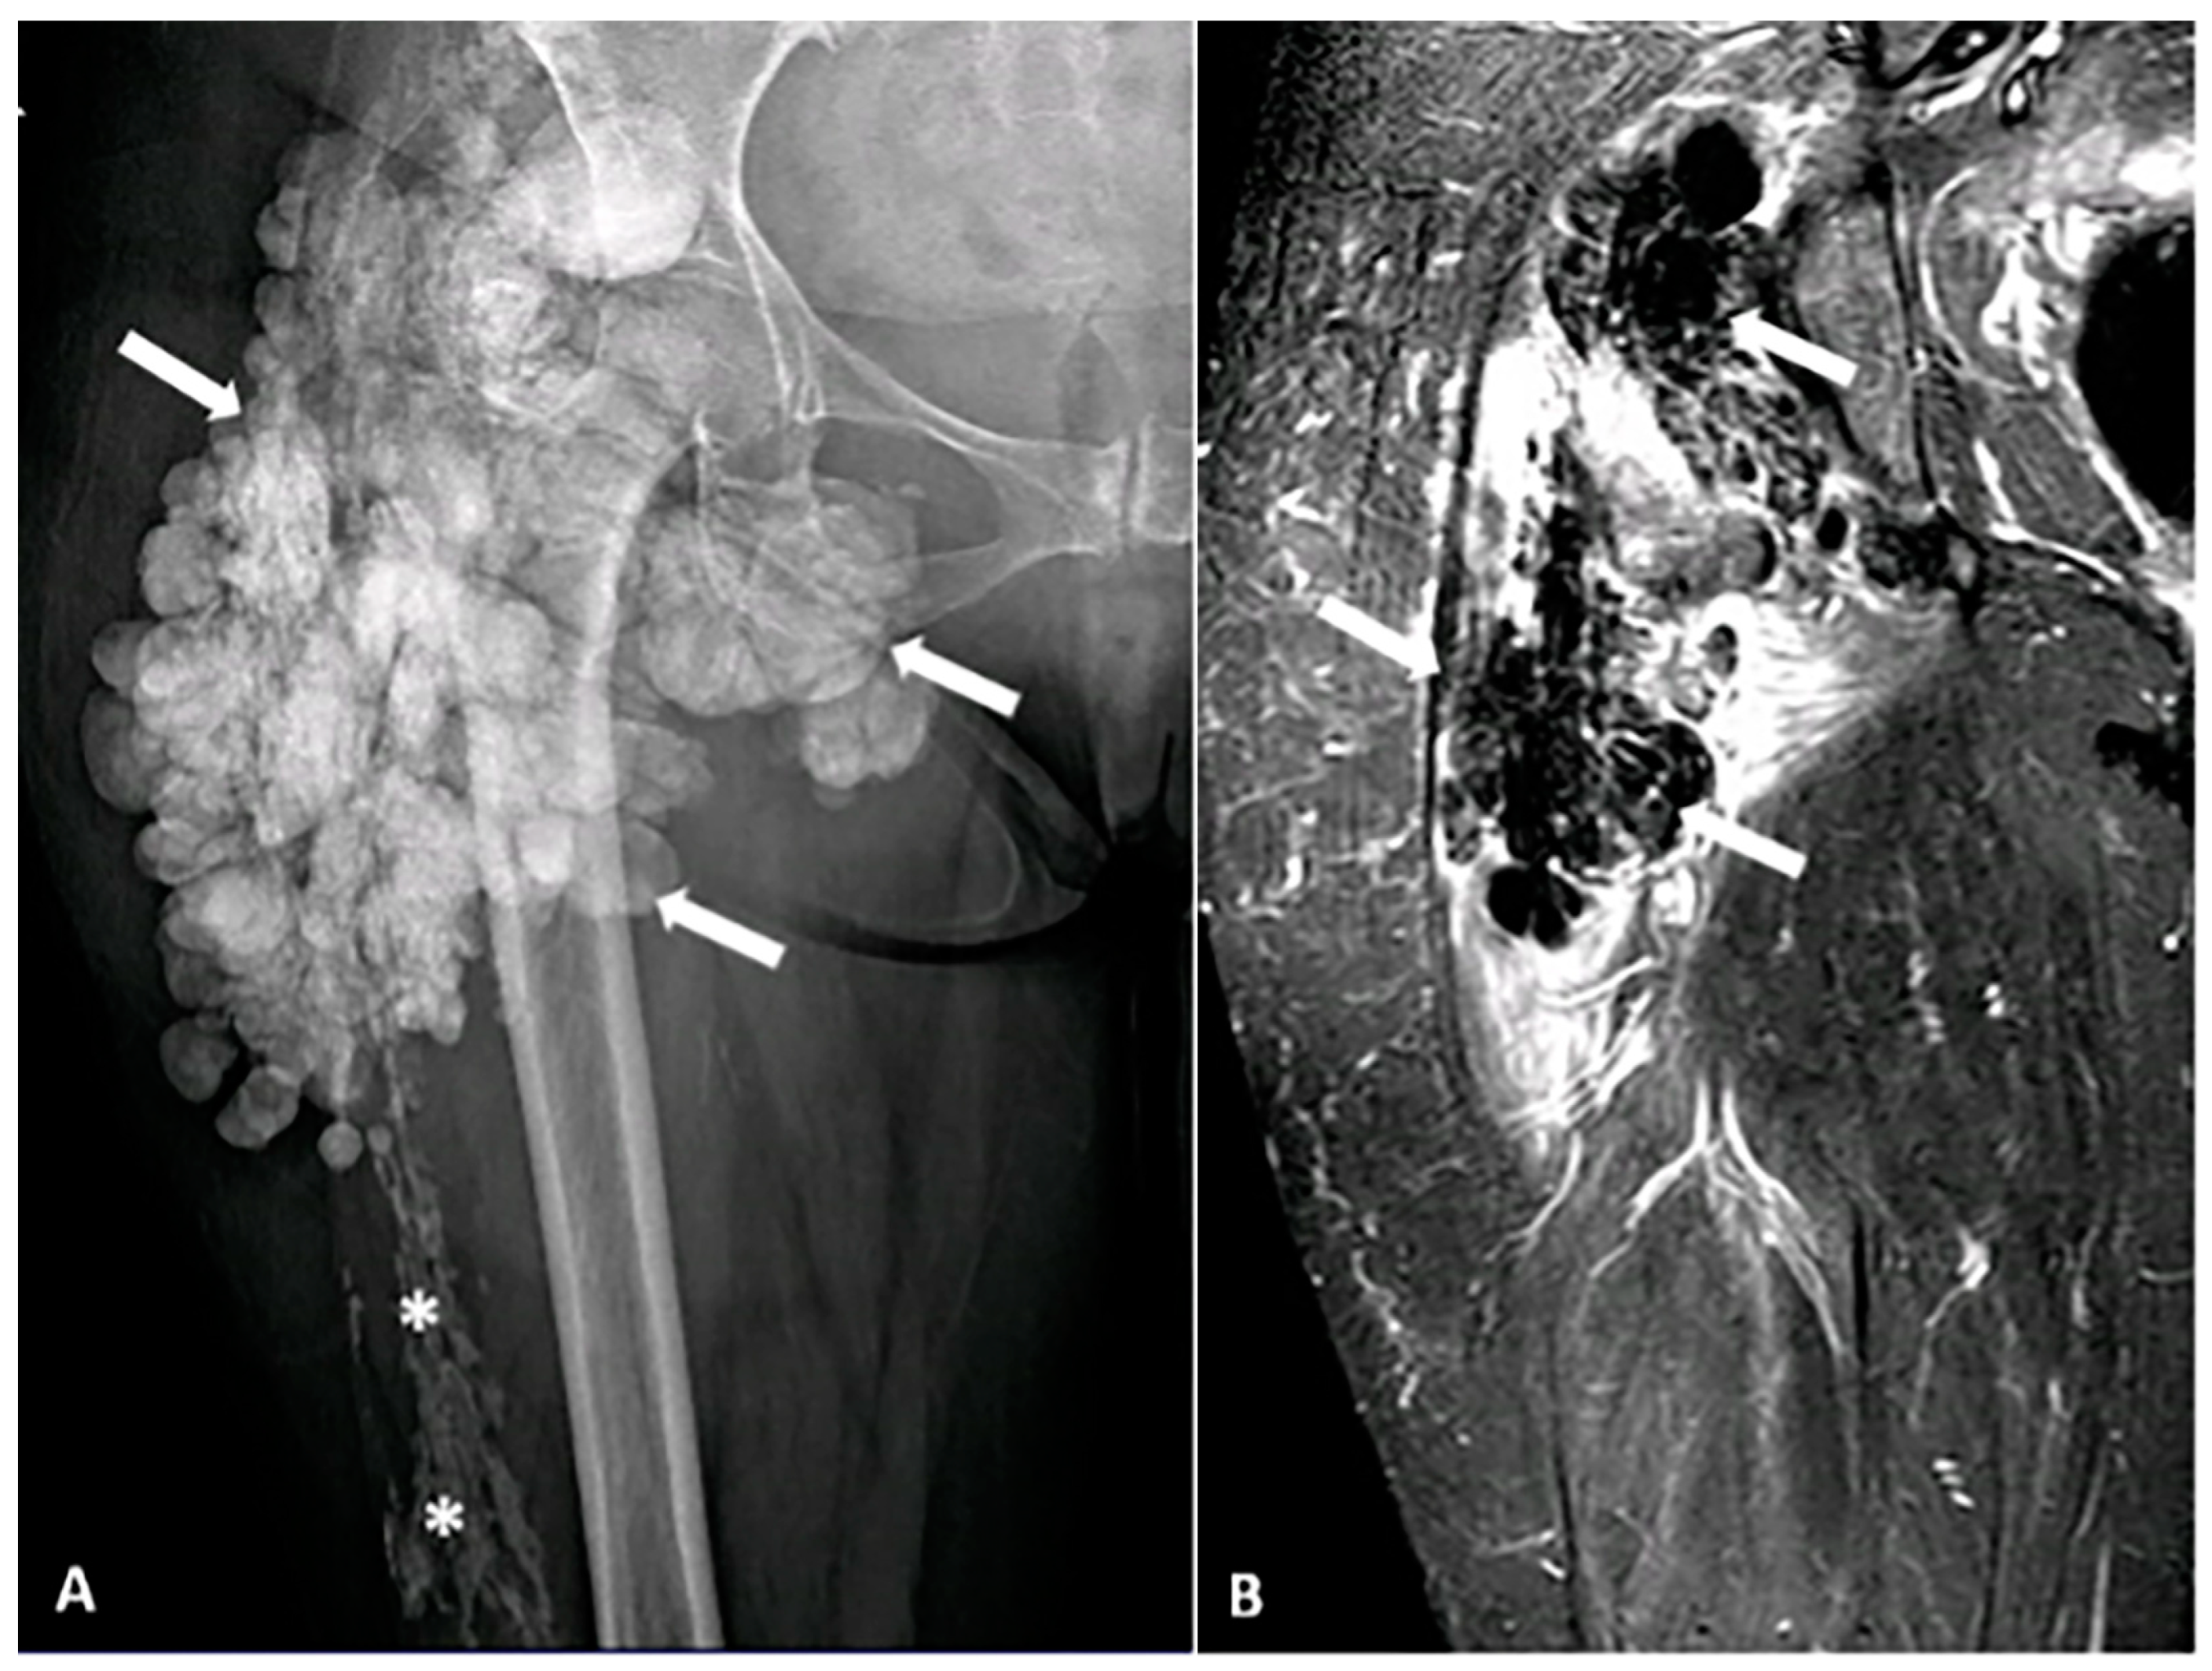

5.2.1. Gout

5.2.2. Primary Tumoral Calcinosis